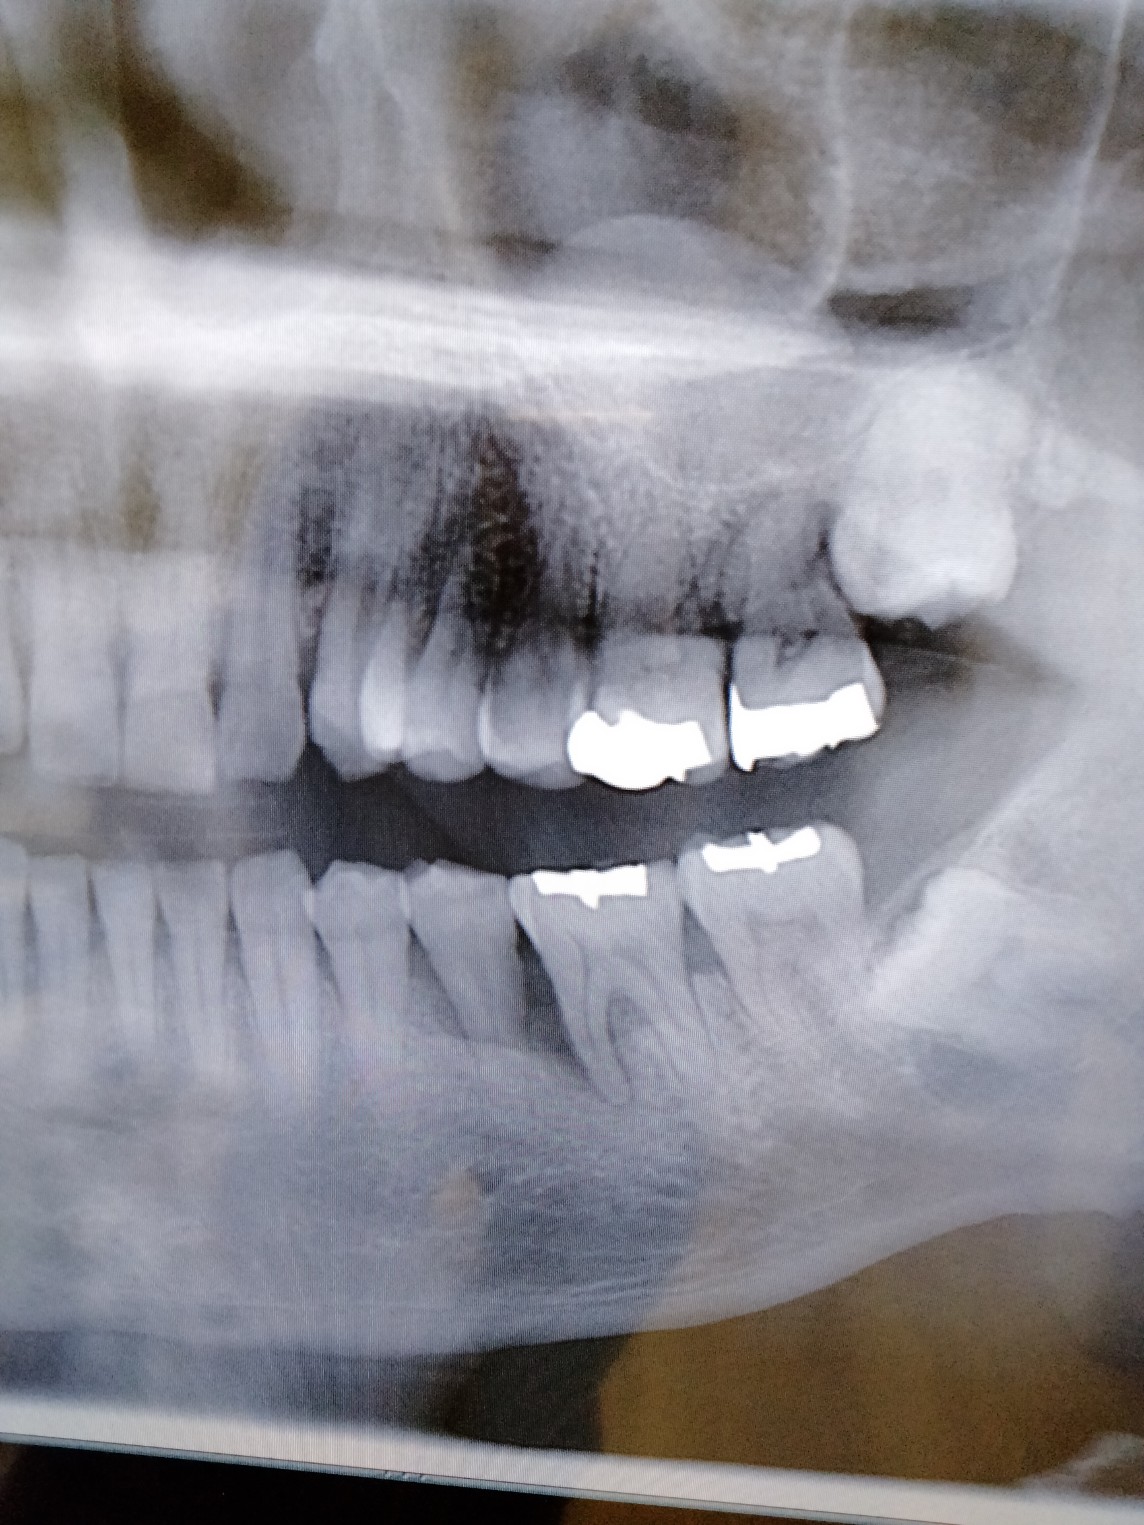

下の左の骨、垂直の骨の溶けかたではないため歯槽骨の再生療法やインプラントは できないと言われたので 下の歯の左側の奥から3番目の歯がグラグラしていますので 抜いた場合 放っておいたら 一番奥の親知らずを含めて大きい 奥歯が3本あるのですが それが移動してくる可能性はあるでしょうか。また こういう 垂直的ではない 骨の溶け方をした際の再生療法は 新しいものは何かないでしょうか? 歯茎を切開してお掃除するだけではダメですよね

画像1IMG20231222161410.jpg

パノラマレントゲンはわかりにくい場合が多々ありますから必要であればC T撮影を追加してもらうなどしてなぜ、その部分に限局した歯槽骨の吸収像があり、その歯がグラついているのか?を診断してもらうのが一般的ではないか?と思いました。

5番だけではなく6番の近心根の周囲の骨の状態も気になります。

5番を抜いたら通常、6番7番が5番側に倒れ込むように移動しますから後にそこの歯も失いやすくなってきます(段階的に総崩れが生じる)。

レントゲンを診たところ歯周病が強く疑われます、歯周病だとすると先ず歯磨き練習をして磨けるようになることが最優先です。

磨けるようになるとこの程度の歯周病なら治癒して歯はしっかりしてくると思います。